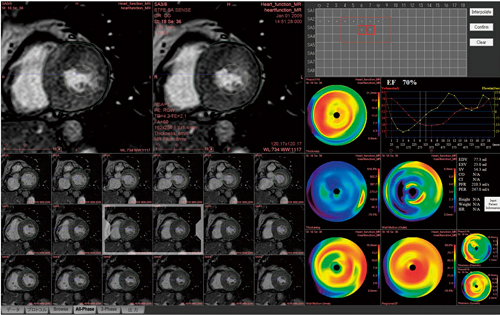

シネMRI,パーフュージョン,遅延造影,BB法などで同じスライス位置を比較観察することは有用であり,心臓MRI検査の大きな利点である。ZIOSTATIONのMR心機能解析のビューワはこれらの画像を並べて表示し,フリック(画像をスクロールする時にマウスで軽くはらう操作)することでストレスのない画像観察が行える(図1)。例えば,遅延造影で心筋壊死の部位や広がりを観察しながら,動画再生した短軸・長軸・4腔像で,壁運動の低下を確認するといった観察方法も有用である。新しく追加された「データ選択アシスタンス」機能では,複数シーケンスのデータを一度に読み込み,あらかじめDICOMタグの情報を登録しておくことで,次回から画像の種類,撮像断面を同じレイアウトで表示することができる。また,複数の異なる名称のシーケンスを登録できるため,異なるメーカーのMR装置で撮像されたデータの解析も可能となり,施設の運用内容に柔軟に合わせることができる。

図1 MR心機能解析のビューワ画面フリックすることで,ストレスのない画像観察が可能

図1 MR心機能解析のビューワ画面

フリックすることで,ストレスのない画像観察が可能